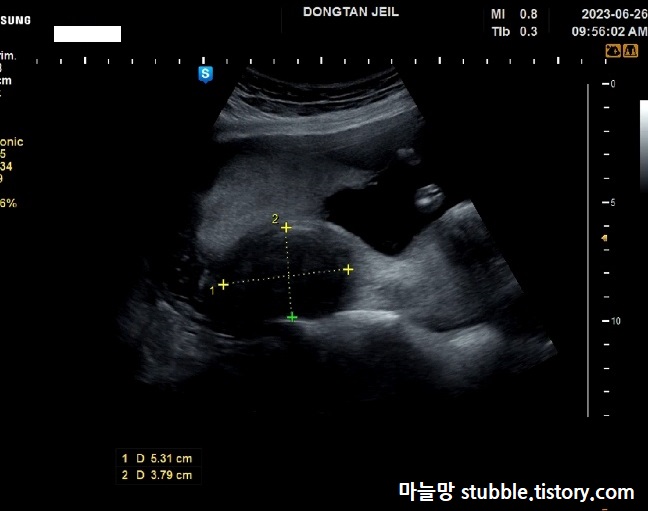

마지막으로 시험관 할 때부터 계속 신경이 쓰였던 근종 사이즈를 재면서 이번 16주 초음파는 마무리가 됩니다.

시험관 이식 전부터 있었던 저의 근종은 배아이식 시점보다 근종이 더 커졌어요. 현재 사이즈 가로길이가 대략 쟀는대도 5.31센티... 원래는 4센티 초반이었습니다. 근종 1호는 자궁 아래쪽에 위치한 걸로 알고 있습니다.

원래 사이즈는 기억이 안나는 나의 자궁 근종 2호.

아마 위치는 착상위치 가까이 있는 것으로 알고 있어요. 시험관 배아이식 할때 근종 2호가 조금만 더 커져도 착상이 잘 안될 수 있는 위치해 있다고 들었었습니다. 역시 아기와 함께 무럭무럭 자라고 있는것 같아요.

담당 의사쌤께서는 재면서 「(자궁근종이)크네요.」라고 말씀하셨지만 크게 문제 되지는 않을 거라고 말씀하셨어요.